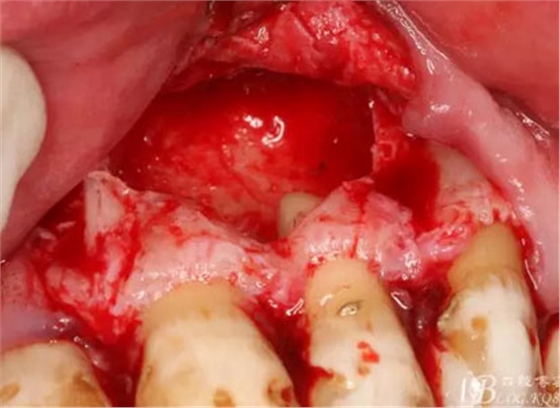

圖12.暴露出的完整囊壁,真夠大!

圖13.完整的從骨壁上剝離囊壁

圖14.呼之欲出的囊腫